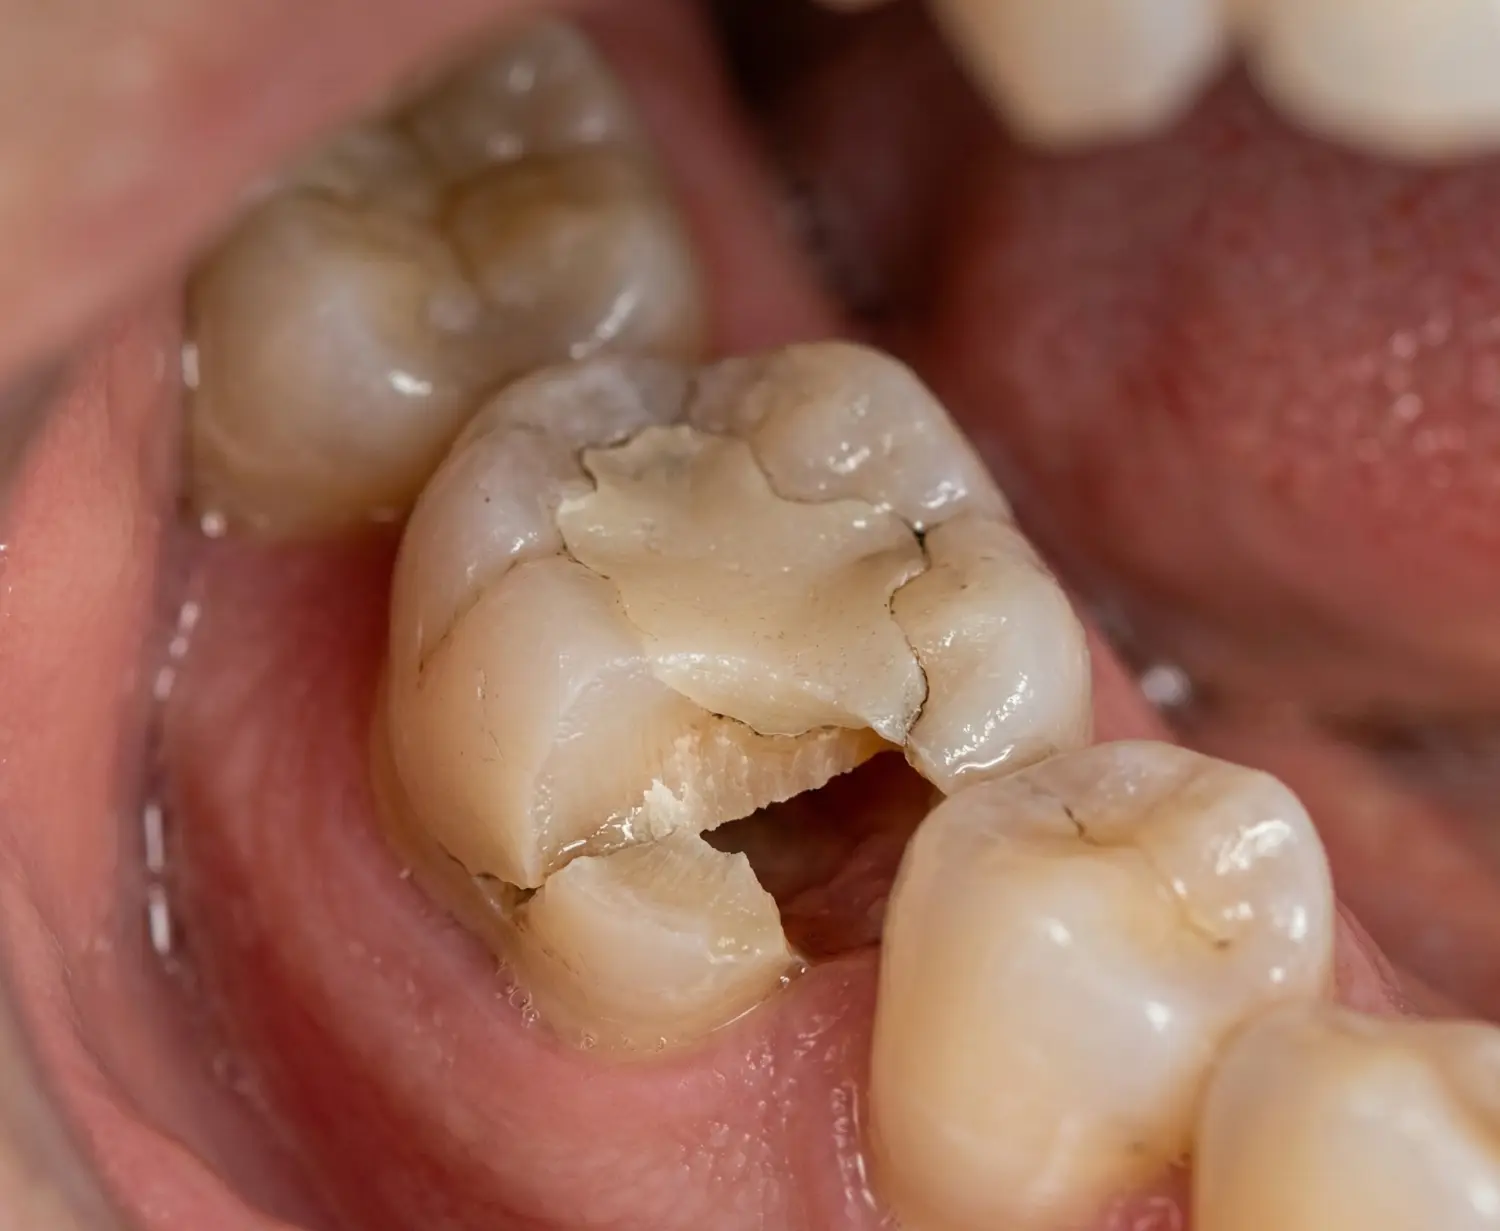

Dolgu Kenarı Kırılan Dişte Belirtiler

Dolgu olan dişin kenarı kırıldığında şu belirtilere dikkat edin:

Görsel Belirtiler

- Görünür çatlak veya kırık hattı

- Dolgunun bir bölümünün ayrılmış olması